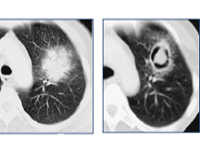

На рентгенограмме инвазивный аспергиллез обнаруживается поздно, поэтому рекомендуется компьютерная томография высокого разрешения. В течение первой недели заболевания при компьютерной томографии легких определяются несколько узлов с характерным венчиком (симптом ореола). Позже, в результате некроза инфильтрата, появляется область просветления в форме полумесяца (симптом мениска).